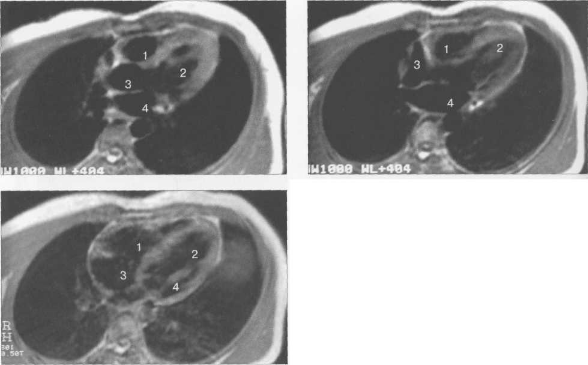

Рис. 9.47. МРТ сердца. Аксиальная плоскость.

Здесь и на рис. 9.48—9.52:

I — правый желудочек, 2 — левый желудочек, 3 — правое предсердие, 4 — левое предсердие, 5 — межжелудочковая перегородка, 6 — межпредсердная перегородка, 7 — задняя стенка левого желудочка, 8 — восходящая часть аорты, 9 — дуга аорты, 10 — нисходящая часть аорты, 11 — легочный ствол, 12 — правая легочная артерия. 13 — левая легочная артерия, 14 — верхняя полая вена, 15 — нижняя полая вена, 16 — трахея.

На рис. 9.47—9.52 представлены Т1-ВИ наиболее часто используемых МР-сечений сердца.